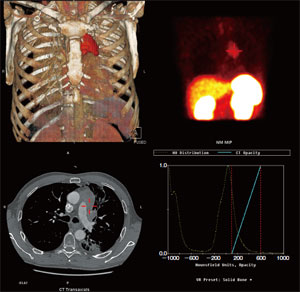

この装置は、1インチのStarBriteクリスタル(図3)と95本のPMT(光電子増倍管)を搭載し、“PET 画像”が撮像できるハイブリッド装置です。一番心配だったのは“画質”です。十数年前に登場したSPECT-PET装置は、511keVを収集できるだけで画像にならず、SPECT側にも悪影響がありましたが、それでは困ります。そこで、導入前にこの装置が実際に稼働している病院の画像を見せてもらいました。この装置では、SPECT とPETの収集モジュールが分かれており、StarBriteクリスタルの効果もあって、SPECT、PETともに満足のいく画質が得られていました。また、PET 画像では、CT による吸収補正の効果が顕著に出ていました(図4)。

図4 PETの臨床画像 a:CT吸収補正あり b:CT吸収補正なし

a:CT吸収補正あり

b:CT吸収補正なし